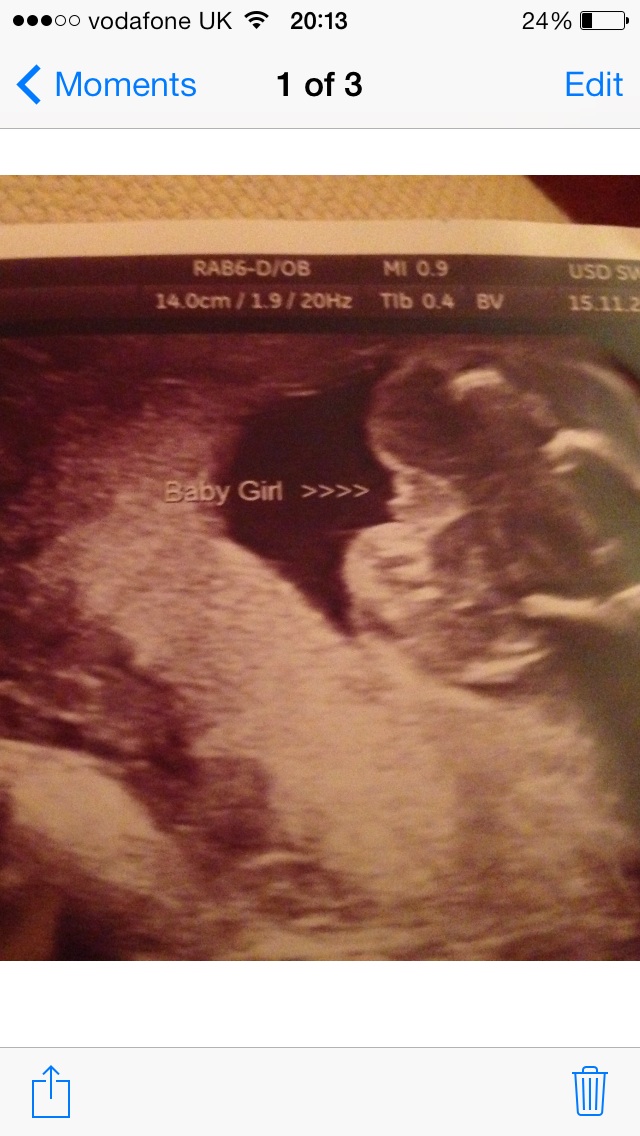

21 week potty shot ultrasound tech says girl, do we agree??Attachment 22538